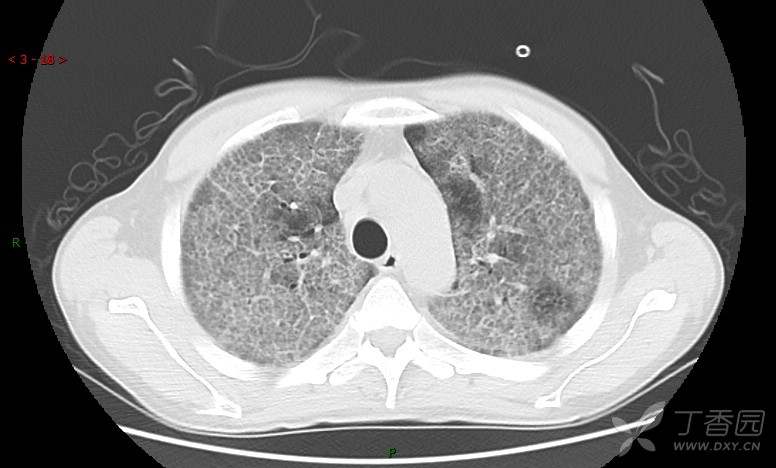

地图+铺路石征=PAP?那升高的CEA怎么说(病例3连发,附其他2例链接)

患者男,42岁,咳嗽半年余,加重伴憋喘2月余。

患者半年余前无明显诱因出现间断咳嗽,干咳为主,偶咳少量黄白痰,剧烈咳嗽或运动后可出现轻度憋喘,无高热、脓臭痰,无胸痛、咯血及晕厥,无低热乏力及盗汗,无心前区压榨感及夜间阵发性呼吸困难,初未在意,未予正规诊治。2月余前患者自觉上述症状较前加重,咳嗽、憋喘明显,黄白色粘痰略有增多,伴有发热,热前伴有畏寒、寒战,体温最高达38.9℃,先后就诊多家医院,入住重症监护室,未行气管插管,考虑“重症肺炎”,给予“美罗培南、复方磺胺甲噁唑”等药物抗感染,“卡泊芬净”抗真菌,并给予“甲泼尼龙”等药物治疗35天,经治疗后症状好转于2018-04-02出院。患者自出院后仅应用中药治疗(具体不详),并给予家庭氧疗,平素仍有间断咳嗽,咳少量黄白色粘痰,活动后憋喘明显,活动耐量差,以卧床为主。

血清肿瘤相关抗原116.22U/ml↑(0--95);

癌胚抗原 61.96 ng/mL ↑ 0--5

神经特异性烯醇化酶 33.12 ng/ml ↑ 0--16.3

细胞角蛋白19片段测定 40.23 ng/ml ↑ ≤3.3